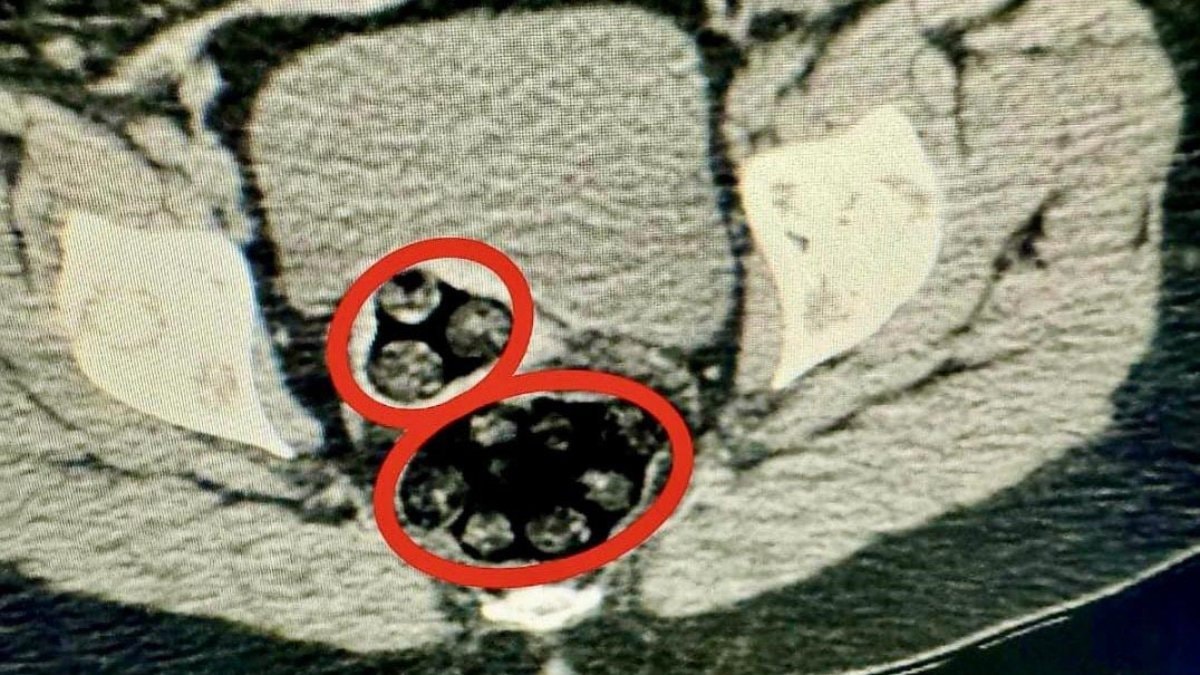

Kars Harakani Devlet Hastanesi'ne götürülen Yenkejeh'in çekilen röntgeninde, makatında uyuşturucu tespit edildi.

Doğal yolla kadının makatından 94 parça halinde toplam 550,93 gram metamfetamin çıkarıldı.